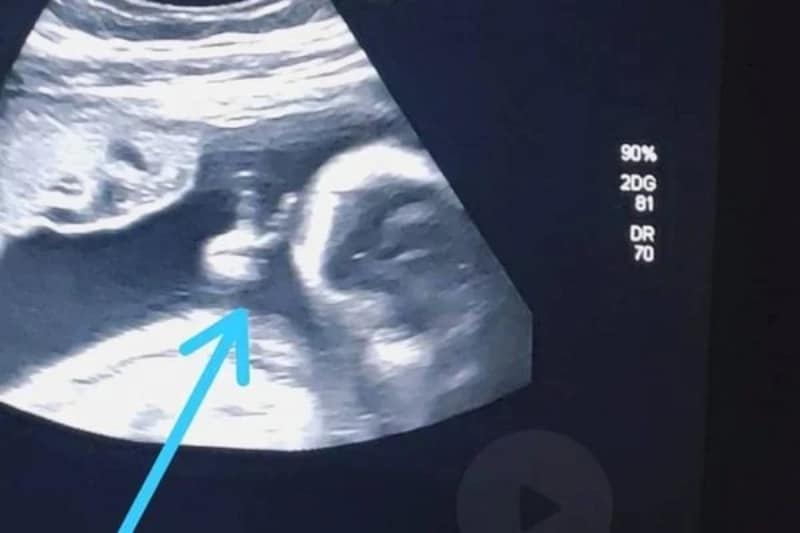

Felipe Moreira dos Santos, de 32 anos, enfrenta um câncer raro no baço e, ao acompanhar o exame de ultrassonografia de sexto mês do primeiro filho, acredita ter recebido um sinal divino. O bebê fez um “V” de vitória com a mão, dentro do útero.

No ultrassom, ele se deparou com a surpresa de ver o filho Davi fazendo um sinal de “V” com uma das mãozinhas. “Até a médica falou: ‘Olha, ele fez o sinalzinho de vitória com a mão’. Eu fiquei sem acreditar”, afirma.